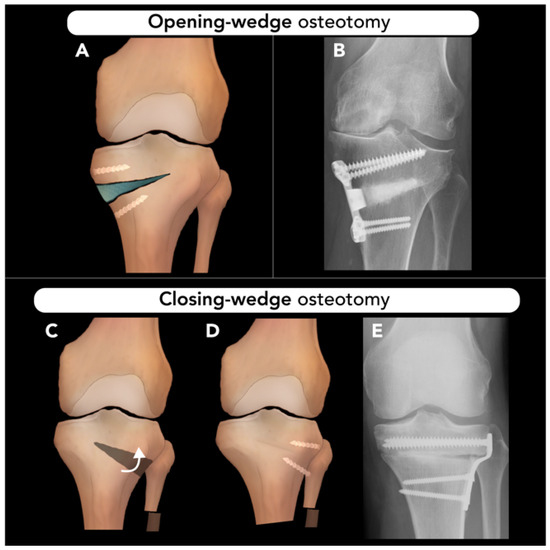

1.2.1. Osteotomy Techniques: Opening-Wedge, Closing-Wedge, and Dome Osteotomies

- Kunze, K.N.; Beletsky, A.; Hannon, C.P.; LaPrade, R.F.; Yanke, A.B.; Cole, B.J.; Forsythe, B.; Chahla, J. Return to work and sport after proximal tibial osteotomy and the effects of opening versus closing wedge techniques on adverse outcomes: A systematic review and meta-analysis. Am. J. Sports Med. 2020, 48, 2295–2304. [Google Scholar] [CrossRef]

- Ruzbarsky, J.J.; Dare, D.M.; Marx, R.G. Closing verses opening wedge high tibial osteotomy: An evidence-based review. HSS J. 2015, 11, 291–293. [Google Scholar] [CrossRef] [PubMed]

- Wu, L.; Lin, J.; Jin, Z.; Cai, X.; Gao, W. Comparison of clinical and radiological outcomes between opening-wedge and closing-wedge high tibial osteotomy: A comprehensive meta-analysis. PLoS ONE 2017, 12, e0171700. [Google Scholar] [CrossRef]